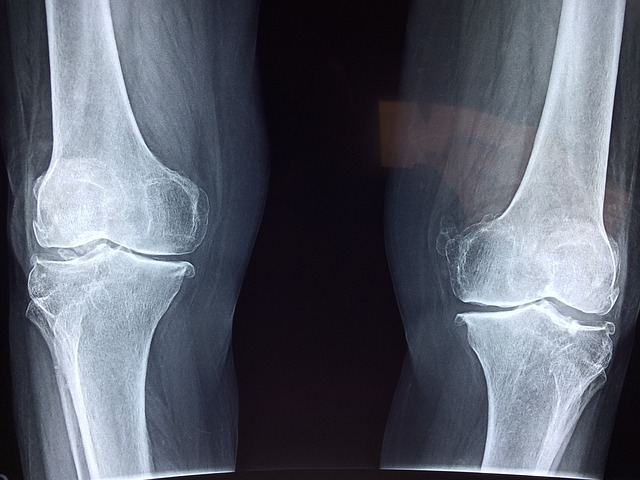

Starzenie się jest naturalnym procesem, który wpływa na zdrowie chrząstki stawowej. Wraz z wiekiem chrząstka stawowa traci swoją elastyczność i zdolność do regeneracji. To zwiększa ryzyko jej uszkodzeń i prowadzi do występowania chorób zwyrodnieniowych stawów, takich jak artretyzm.

Choroby zapalne, takie jak reumatoidalne zapalenie stawów, mogą prowadzić do uszkodzeń chrząstki stawowej. Stan zapalny w organizmie wpływa negatywnie na zdrowie chrząstki, prowadząc do jej degeneracji i uszkodzeń.